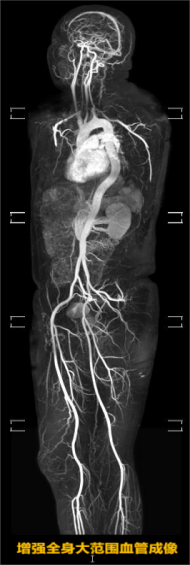

而且,磁共振检查优势明显,需求量大。相对于X光、CT来说,磁共振显像更为清晰,对实质器官、神经、血管、韧带、肌肉等检查有非常高的分辨力,诊断精准。其主要原理是利用磁场对人体细胞核激发而成像,没有X射线,对人体没有电离辐射伤害,很多情况下磁共振检查能够更清楚地了解病情,整体需求量远远超出医院运转量。

为了进一步提高检查效率,科室还升级了相对分设备检查。放射科主任邱迎伟表示,相对分设备检查是根据设备优势和检查部位进行分类,也就是不同部位的检查用不同设备来做,物尽其用。比如神经、血管优势品牌设备,对于全身大范围血管显像更全面,外周神经显示清晰;还可以在无对比剂下成像,不打药更安全。